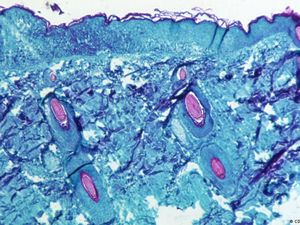

WHO mengabarkan sudah ada 9.200 kasus cacar monyet di 63 negara. Komite darurat akan segera mengkaji tindakan pencegahan dan cara mengatasi wabah tersebut.